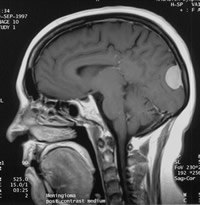

3.MRI檢查 大多數腦膜瘤的信號與腦灰質相似,在T1加權像上多數為等信號,少數表現為低信號;在T2加權像上可表現為高、等、低信號,注射Gd-DTPA後絕大部分腫瘤出現強化,大部分腦膜瘤與相鄰腦組織特別是腦幹有包膜相隔。另外MRI在顯示腦膜瘤與鄰近血管關係上明顯優於CT,可以用三維立體方式清楚地顯示腫瘤的位置、大小,腫瘤的侵犯方向,有無基底動脈及分支受累。更重要的是在T2加權像上, 可觀察瘤周的蛛網膜層是否存在,有無腦幹軟膜侵犯, 有無腦幹水腫,這對於疾病的術前評估是十分重要的(圖1) 當腦膜瘤包繞或擠壓頸內動脈、基底動脈時,由於血管內快速流動的血液產生流空現象,在T1和T2加權圖像上均為低信號區。